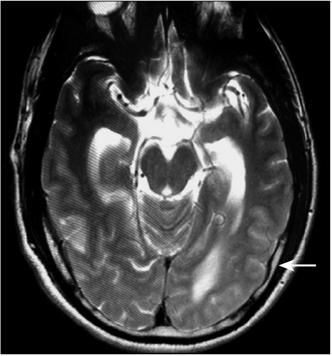

检查回报:血清铁蛋白(肿瘤标志物之一)360μg/L,升高。腰穿提示脑脊液压力>330mmH2O,细胞总数4个/μl,白细胞数2个/μl,糖正常,氯化物111mmol/L,降低,蛋白120mg/dl,升高。细胞学检测可见散在异形大细胞,可疑肿瘤细胞。颅脑磁共振(2007年7月4日)平扫提示脑实质未见异常,幕上脑室略扩大,增强后提示部分脑膜强化,静脉相提示上矢状窦末端及直窦血管粗细不均,似有部分血栓(图2)。经DSA(2007年7月12日)证实下矢状窦、直窦未显影,上矢状窦中段显影差,考虑静脉窦血栓形成(图3)。

图2 颅脑磁共振:提示部分脑膜强化(箭头)